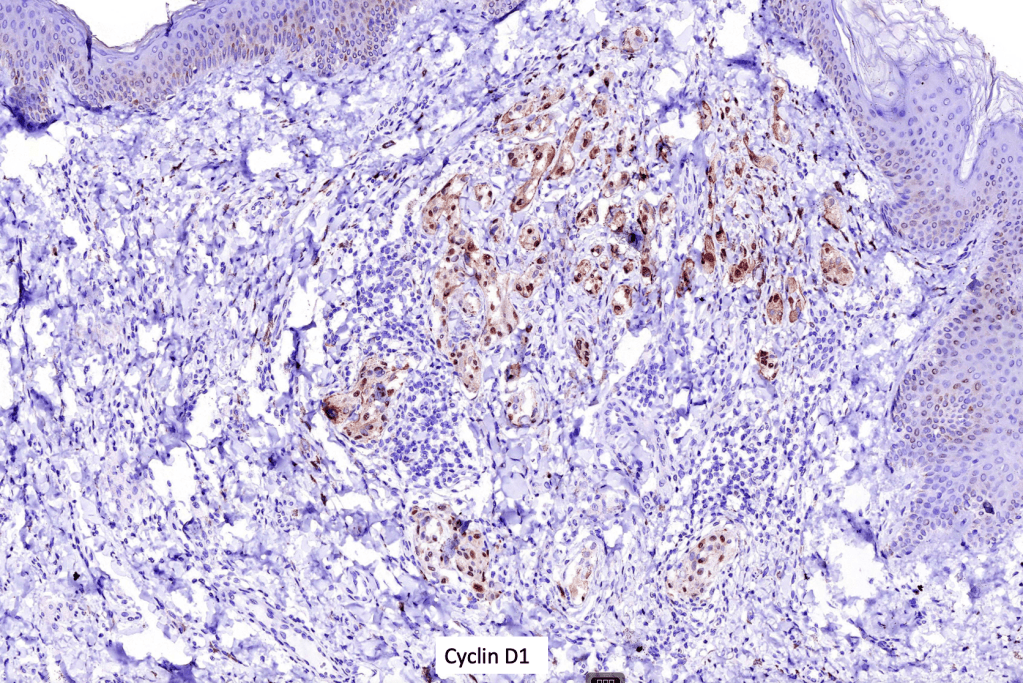

•Strong nuclear & cytoplasmic expression of β catenin, cyclin D1 & LEF1